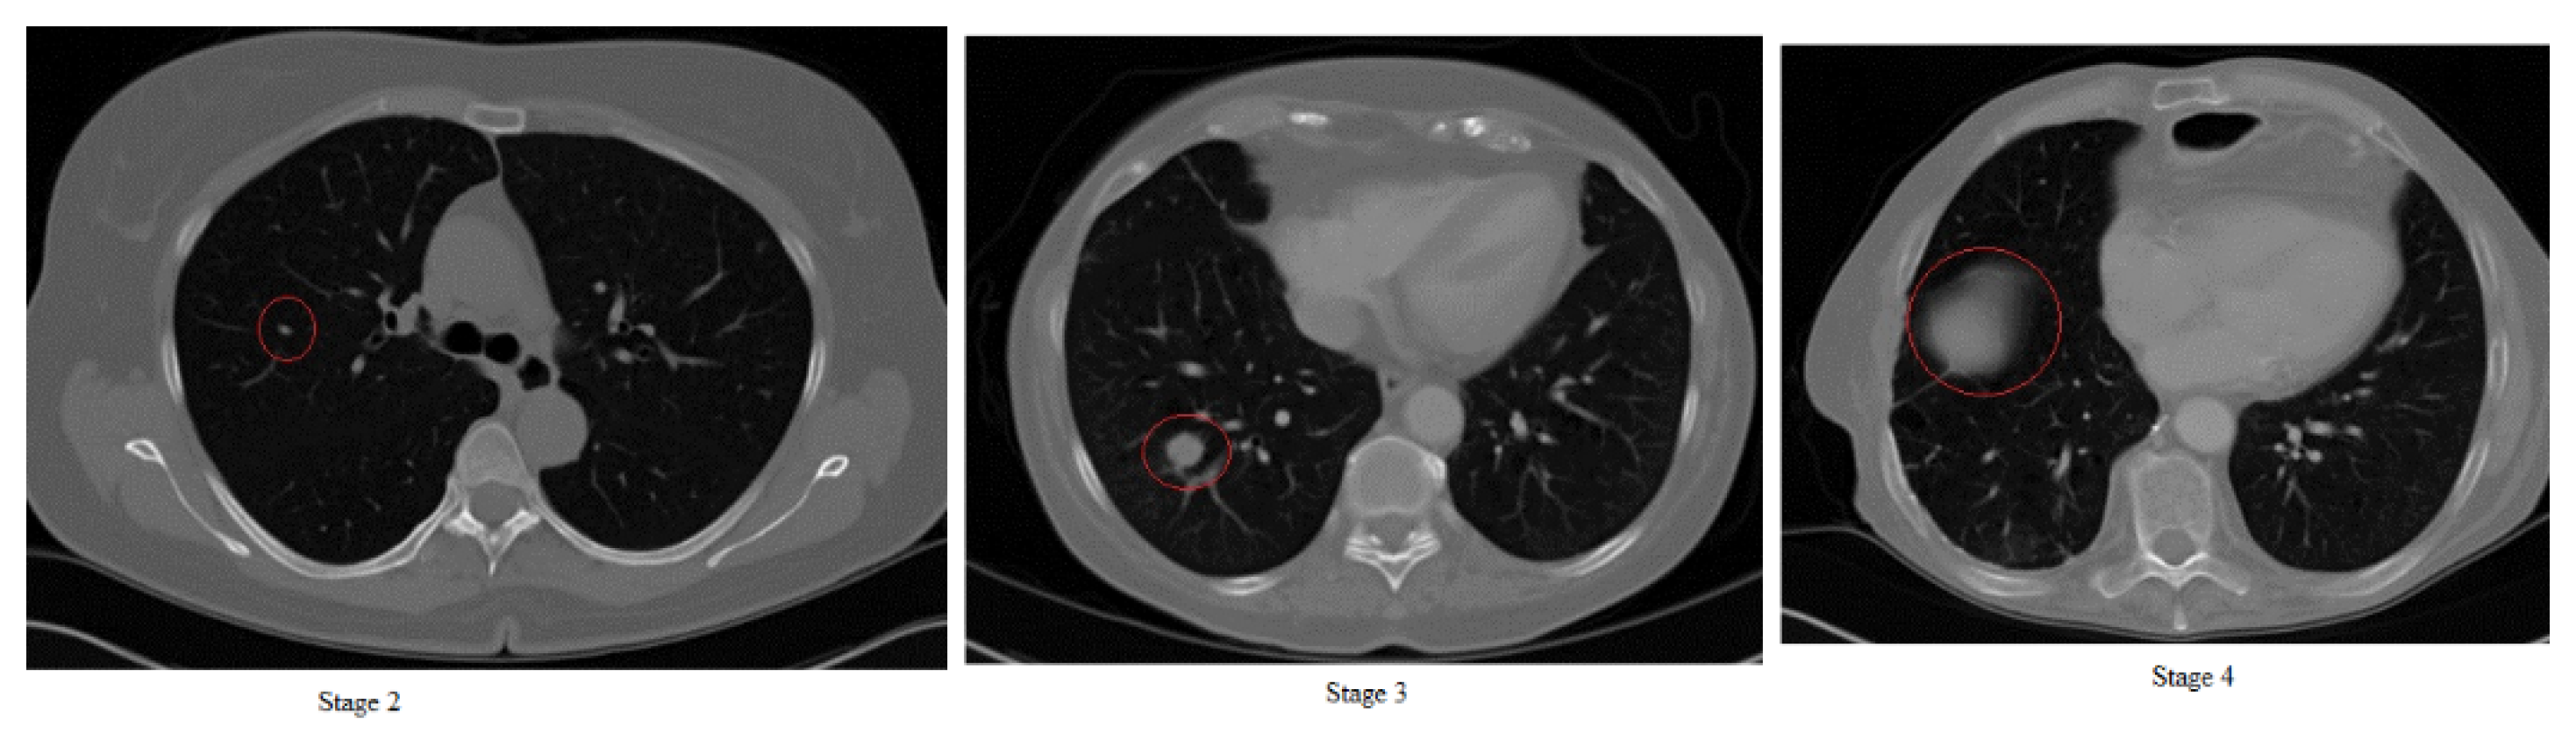

4. Tx Stages of Lung Cancer of Our Double CDNN

After defining, training and testing our network (Section 3.2), we used the topologies of the regular and double CDNN in experiments with an additional dataset from 35 patients diagnosed with lung cancer in stages 2, 3 and 4 (images obtained from the medical hospital in Tetovo, Macedonia). Since it is difficult to obtain images in stages 0 and 1, we found 35 patients whose possibility of cancer was diagnosed in stage 2 and recorded up until late stage 4. In Figure 7, we can see example CT images of stages 2, 3 and 4 of lung cancer.

Figure 7.

Stages 2, 3 and 4 of lung cancer.

From CT scan images, doctors can diagnose the stage only by using the size of the tumor (and in some cases the position of the tumor). Stage 2 (first image in Figure 7) shows the tumor in red circle on the left side, which in real size is around 4 cm. Stage 3 (second image in Figure 7) shows the cancer in red circle. In this stage, the tumor is larger than 4 cm and is in the middle of the lung and/or going towards the outer parts of the body. We can see in the second image in Figure 7 that the tumor is in late stage 3 since it leans towards the outer parts of the lungs. Stage 4 is in the third image in Figure 7 and we can see that the size of the tumor is covering large portions of the lung and is almost in the outer parts of the body and lung. This outer part of the lung is called area 1 and if the tumor is in this area (shown with red circle in the third image in Figure 7), it means that the cancer is terminal.